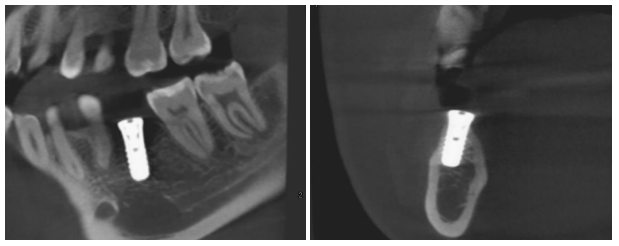

治疗过程:46必兰局麻下,切开翻瓣,预备种植钉道,植入ITI4.8*10mm种植体一枚,颊侧植入Bio-oss骨粉,覆盖骨膜,严密缝合。

备洞+植入植体

植入植体X线